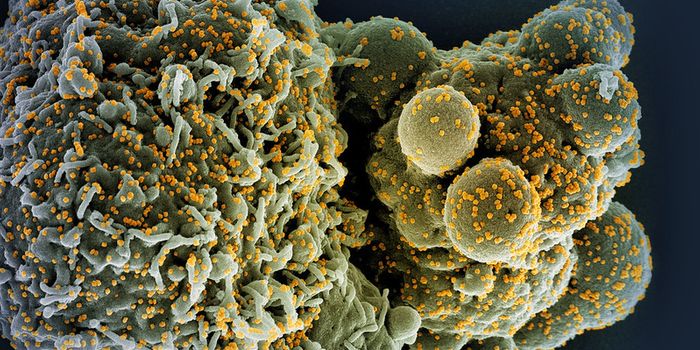

SEP 08, 2024MicrobiologySARS-CoV-2, the pandemic virus that causes COVID-19, has mutated endlessly since it burst on the scene in late 2019. An ...

AUG 27, 2024MicrobiologySince the start of the COVID-19 pandemic, the virus that causes the illness - SARS-CoV-2 - has had a practically infinit ...